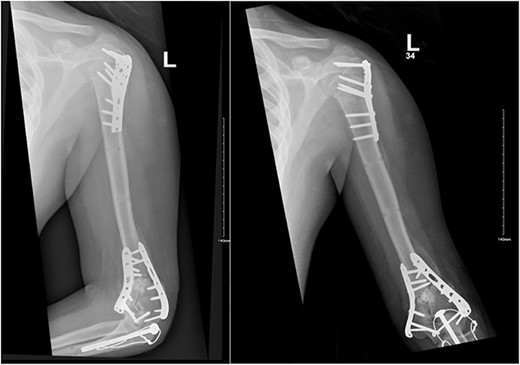

A 14-year-old boy with unknown medical and surgical history was brought by the emergency medical services to the emergency department as a case of multiple trauma after a MVA. Upon arrival, primary and secondary surveys were conducted, and management followed accordingly. After stabilization, all related specialties were involved in case management. Multiple fractures were detected, including left mandible, acetabular, open femur, and humerus fractures, as well as a comminuted pelvic fracture. The humerus fractures involved the proximal and distal area, as shown in Fig. 1.

Anteroposterior (AP) view of the left humerus and elbow pre-operative.